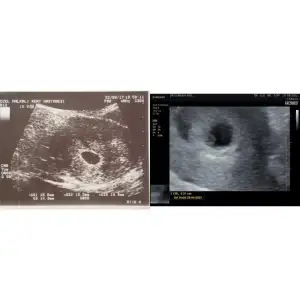

2017 doğumlu bir oğlum var onunla usg fotoğraflarına bakarken farkettim ki onda da ilk 5hafta 5 günlükken doktora gitmişim. Şimdi de öyle oldu ikisinde de usg de 5hafta 5 gün yzıyor😍 yan yana koyuyorum soldaki oğlumun ilk usg si sağdaki şuanki bebeğimin. Ramzi teorisine göre oğlumun ki tutuyor mu sizce. Şuan ki ne oluyor ozaman♥️

Ok işaretiyle gösterdiğim yerlere bakıyor bence yönü. Öyle düşünince ilkinin erkek olduğu çıkar bu teoriye göre. Doğrulanmış oluyor. Eğer ki yorumum yanlış değilse. Bu durumda 2.si de erkek gözüküyor. Diğer arkadaşlar nasıl yorumlar bilmiyorum😇

İkinci kare de erkek duruyo canım ramzi teorisine göre bakabilirsn sende birinci kareye bak

Ben tam anlamıyorum canım. İlk fotoğrafta bebeğin nerde olduğunu göremedim ama ikinci fotoğraftaki şimdiki bebiş ramzi teorisine göre erkek konumunda galiba :)